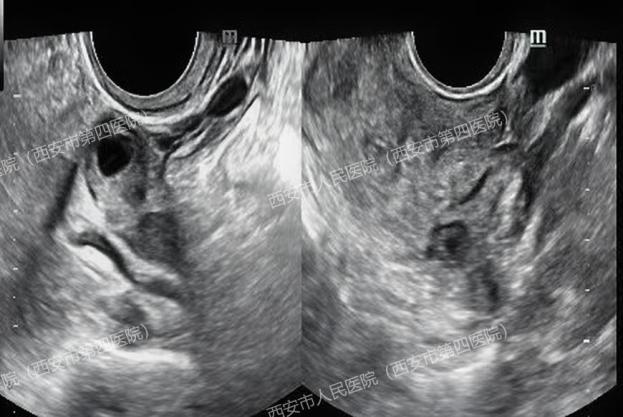

关医生仔细扫查发现:

子宫内未见明显孕囊,右侧卵巢内小囊肿,双侧附件区未看见其他包块。通常,人绒毛膜促性腺激素(HCG)达到1000~2000mIU/ml左右就能看到孕囊,但王女士的HCG水平上升到90000mIU/ml时,超声却没有提示宫内孕囊。理论上来说即使真的宫外孕,包块应该很大、很明显,一眼就能找到才对啊?

医生觉得疑惑,耐心安抚患者的同时又全面细致的沿子宫周围及上方扩展了扫查范围,当扫查到肝脏时,顿时惊呆了......